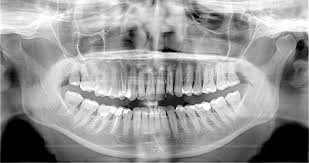

Panoramique dentaire numérique 3D au capteur plan dynamique sans Céphalométrie

Rotograph prime 3D

Rotograph Prime 3D est la nouvelle unité 3D panoramique dotée de la technologie CBCT, l’évolution naturelle du succès commercial de Rotograph Prime, qui conserve son design épuré et particulier, sa structure mécanique légère, son ingénieux système de montage mural et ses capacités d’imagerie 2D. Comme Prime, Rotograph Prime 3D a été conçu comme outil de diagnostic complet, permettant une transition plus facile vers les technologies d’imagerie dentaire les plus évoluées grâce à un investissement abordable pour tous.